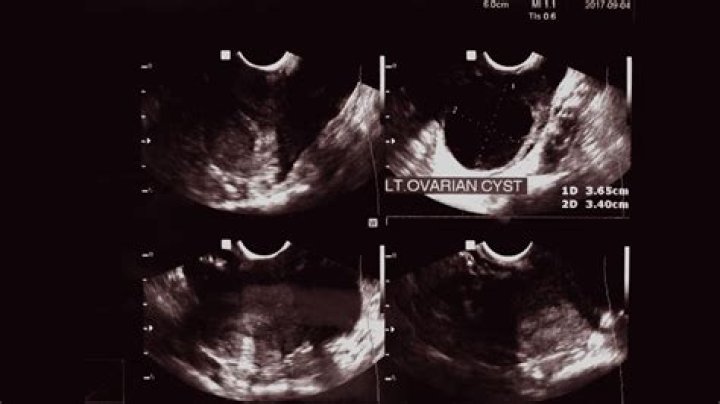

When women experience pelvic pain and abnormal bleeding, doctors can use ultrasound imaging to help find the cause. These scans often also find growths in the ovaries. The most common type, called a simple cyst, isn't usually harmful.

Ovarian cysts can sometimes be detected during a pelvic examination, although an imaging test, usually a pelvic ultrasound, is necessary to confirm the diagnosis. Computed tomography (CT) scan or magnetic resonance imaging (MRI) are also sometimes used, but less commonly.

If your gynecologist suspects that your symptoms could be due to ovarian cysts the best way to diagnose these cysts is through a pelvic exam or by performing an ultrasound. The ultrasound will allow your doctor to examine the abdomen in detail to see if cysts are present.

2. Ultrasound. An ultrasound can pinpoint the location, size, and makeup of ovarian cysts. ...